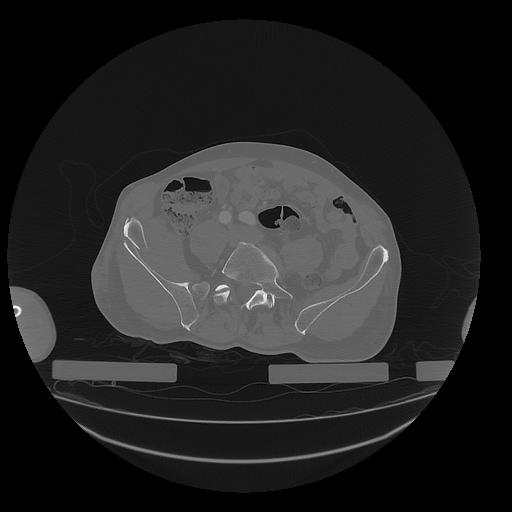

31 PULMON,CE,Vol,1.0,PULMON,,